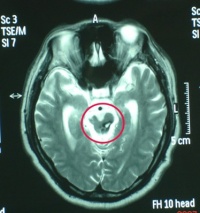

右侧颞叶脑挫裂伤

CT扫描

对脑挫裂伤与脑震荡可以作出明确的鉴别诊断,并能清楚地显示脑挫裂伤的部位、程度和有无继发损害,如出血和水肿情况。同时,可根据脑室和脑池的大小、形态和移位的情况间接估计颅内压的高低。尤为重要的是,对一些不典型的病例,可以通过定期CT扫描,动态地观察脑水肿的演变或迟发性血肿的发生。近年来,在有此设备的医院CT已作为急性头伤的常规检查,因为单靠伤史和查体难以作出超早期诊断。Stein等(1990)指出在GCS13~15危害较小的轻型头

右额颞叶脑挫裂伤合并蛛网膜出血

伤中,首次CT的阳性发现率竟占18%,并有5%需行手术治疗,强调早期CT检查的必要性。

MRI(磁共振成像

一般少用于急性颅脑损伤的诊断。MRI成像时间较长,某些金属急救设备不能进入机房,躁动病人难以合作,故多以CT为首选检查项目。但在某些特殊情况下,MRI优于CT,如对脑干、胼胝体颅神经的显示;对微小脑挫伤灶、轴索损伤及早期脑梗死的显示;以及对血肿处于CT等密度阶段的显示和鉴别诊断方面,MRI有其独具的优势,是CT所不及的。